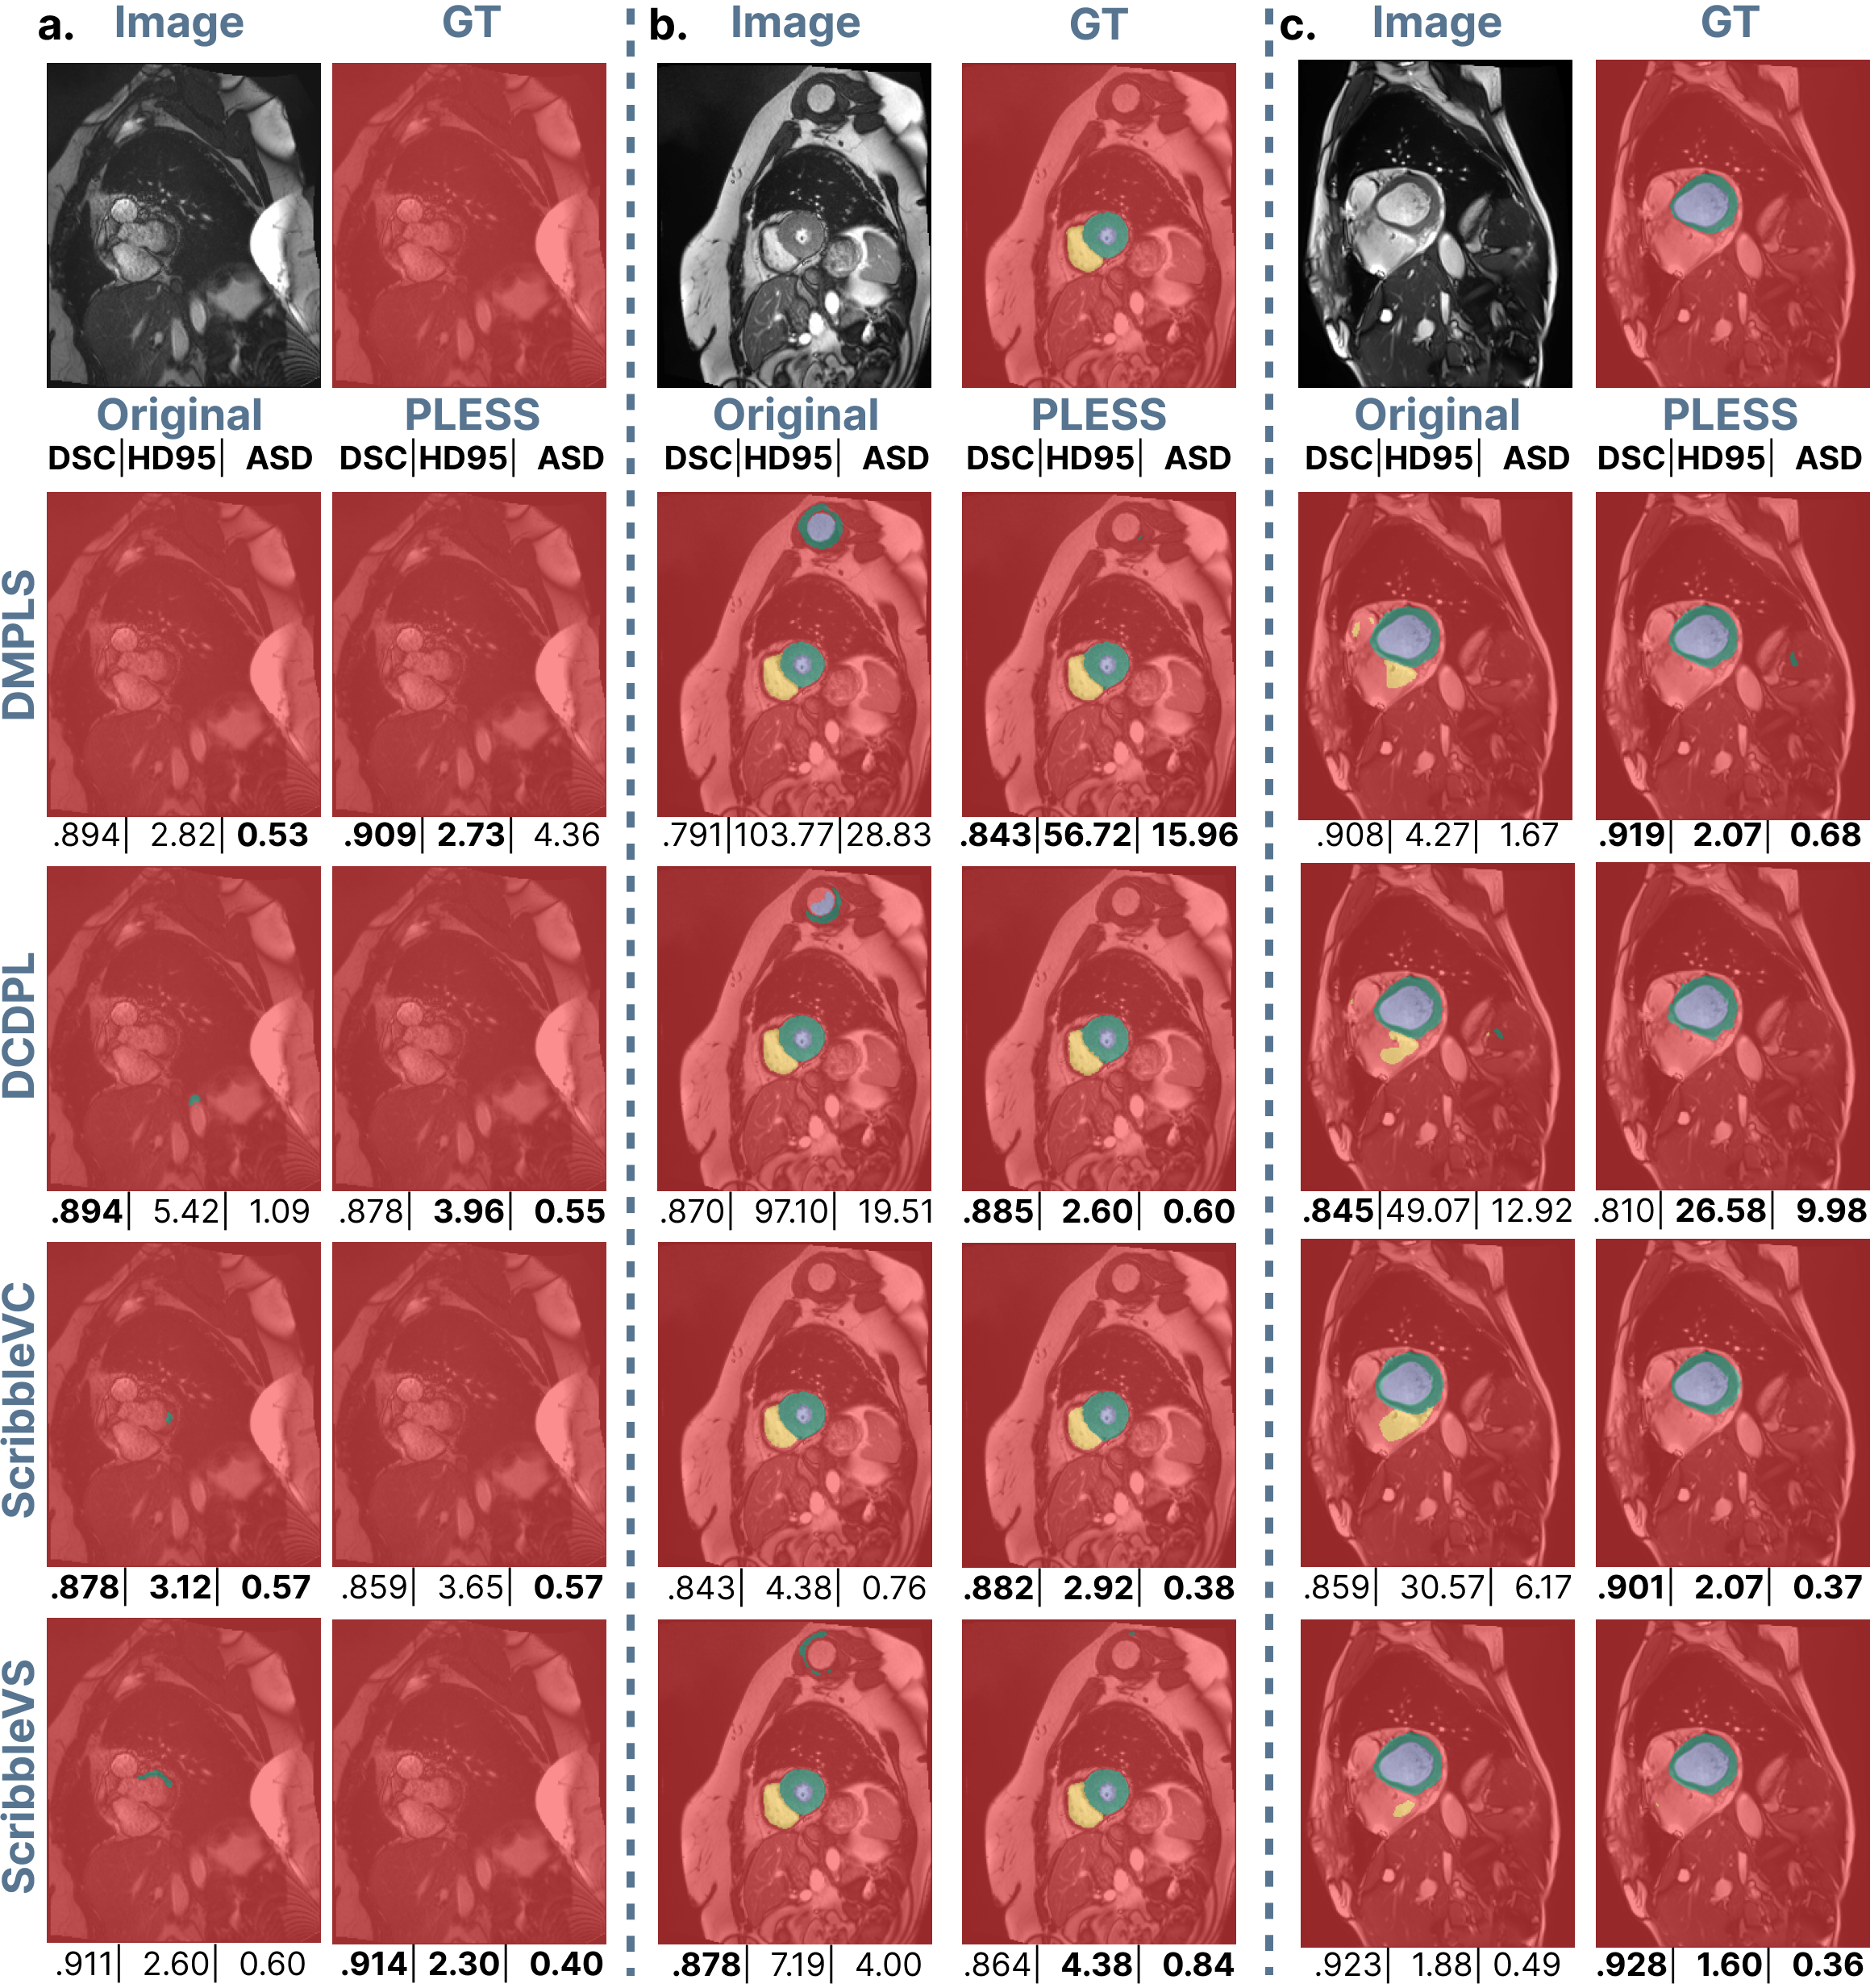

Refer to caption

Fig. 2: Comparison of segmentation performance using the baseline and PLESS on three scans (a, b, c) from the ACDC dataset. Row 1 displays the original MRI slice and ground truth (GT), while subsequent rows show segmentation results from different models: DMPLS [12], DCDPL [18], ScribbleVC [8], and ScribbleVS [17]. Reported DSC, HD95, and ASD scores refer to the whole 3D scan. Label colors: background  , right ventricle (RV)  , myocardium (MYO)  , and left ventricle (LV)  .

A qualitative comparison of the performance of all four segmentation methods on the ACDC dataset is presented in Fig. 2. For each image and each method, results for both original and PLESS setups are shown. In most cases, PLESS leads to improvement in boundary delineation, evident by the improved ASD and HD95 scores.

The three examples in Fig. 2 illustrate representative failure cases of the original setup that are mitigated by PLESS. In example (a), for slices where a particular anatomical structure is not present, the original setup for DCDPL, ScribbleVC, and ScribbleVS frequently produces false positive predictions, most notably for the myocardium (MYO). In contrast, with the PLESS setup these errors are fixed.

In example (b), the original setup incorrectly segments regions that visually resemble the target structure, even though they are anatomically unrelated. This is observed for DMPLS, DCDPL, and ScribbleVS, where regions with similar appearance or geometry are mistakenly labeled. The PLESS setup substantially reduces these errors, suggesting that the propagated labels provide stronger spatial and contextual information, which helps the algorithms differentiate between similar-looking structures.

In example (c), when only two of the three cardiac structures are present in a slice, the original setup often hallucinates the missing third class. This behavior is observed across all four methods and reflects a common limitation of weak supervision, where models tend to over-predict plausible anatomical classes. With PLESS, these false positive segmentations are reduced. These qualitative results show that PLESS improves not only segmentation accuracy, but also the robustness of predictions in challenging and ambiguous cases.